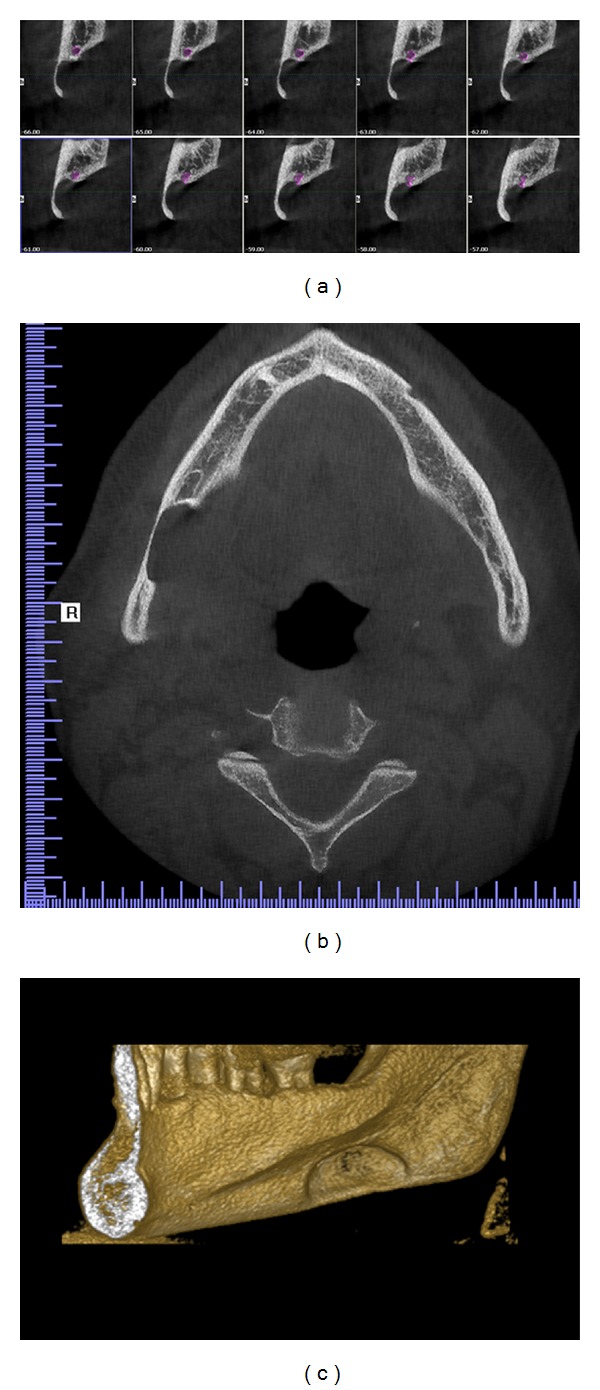

Figure 4.

CBCT images: (a) sagital view displaying continuous 1 mm width sections, (b) horizontal view displaying the cavity outline, and (c) 3D reconstruction of the right mandible displaying buccal cortical bone reduction.

A 57-year-old asymptomatic male patient was referred to Istanbul Medipol University, Faculty of Dentistry, Department of Dentomaxillofacial Radiology in order to undergo routine periodontal treatment. Medical history and dental history were not contributory. Defect of the right mandibular corpus was detected during routine panoramic imaging. Palpation of the defect was not painful with no discomfort. Cone beam computerized tomography (CBCT) was found appropriate for further evaluation. Results showed an oval-shaped, radiolucent area of cystic aspect. This lithic area, located under the lower right second and third molar. The lower wall of the mandibular canal was visible within the radiolucent area showed that there could be a neighboring relationship, but not an involvement, of the inferior alveolar nerve (Figure 3). Lingual wall of the basal bone displayed involvement of the lesion and dimensions of the defect were 22.5 × 10 × 5.5 mm depth (mesiodistal length, inferosuperior height, and buccolingual depth).